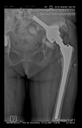

The radiological examination allowed us to verify the close bone-to-implant contact and the unchanged position of the implant during follow-up.

In all the cases operated with the above-described targeting procedure, the stems of the cups remained between the cortical bone surfaces without perforation of the linea terminalis, as shown by postoperative radiographs. There were no complicated surgical situations. In 16 cases, the wound healings were uneventful, and the hips were able to bear weight again after postoperative rehabilitation.

The only patient who suffered an infection healed after the removal of the implant. This complication rate is known and in line with accepted values.

One septic complication occurred. This complication rate is consistent with other revision techniques. In this case, the implant had to be removed, and the patient remained in Girdlestone condition. In such cases, removal of the implants and, of course, surgical debridement and antibiotic treatment are essential. The condition after resection is called Girdlestone’s condition. We had no other complications or unexpected outcomes.

At the time of the manuscript edition, some cases reported in this study were still in the early postoperative period. Even the shortest 10-month follow-up means that patients’ wound healing was uninterrupted, and the implant was securely fixed. By this time, patients are beyond successful rehabilitation. Of course, as with all such patients, monitoring will continue at annual check-ups. Report on the mid and long-term outcomes, gait analysis, and subjective assessments of patients is planned.